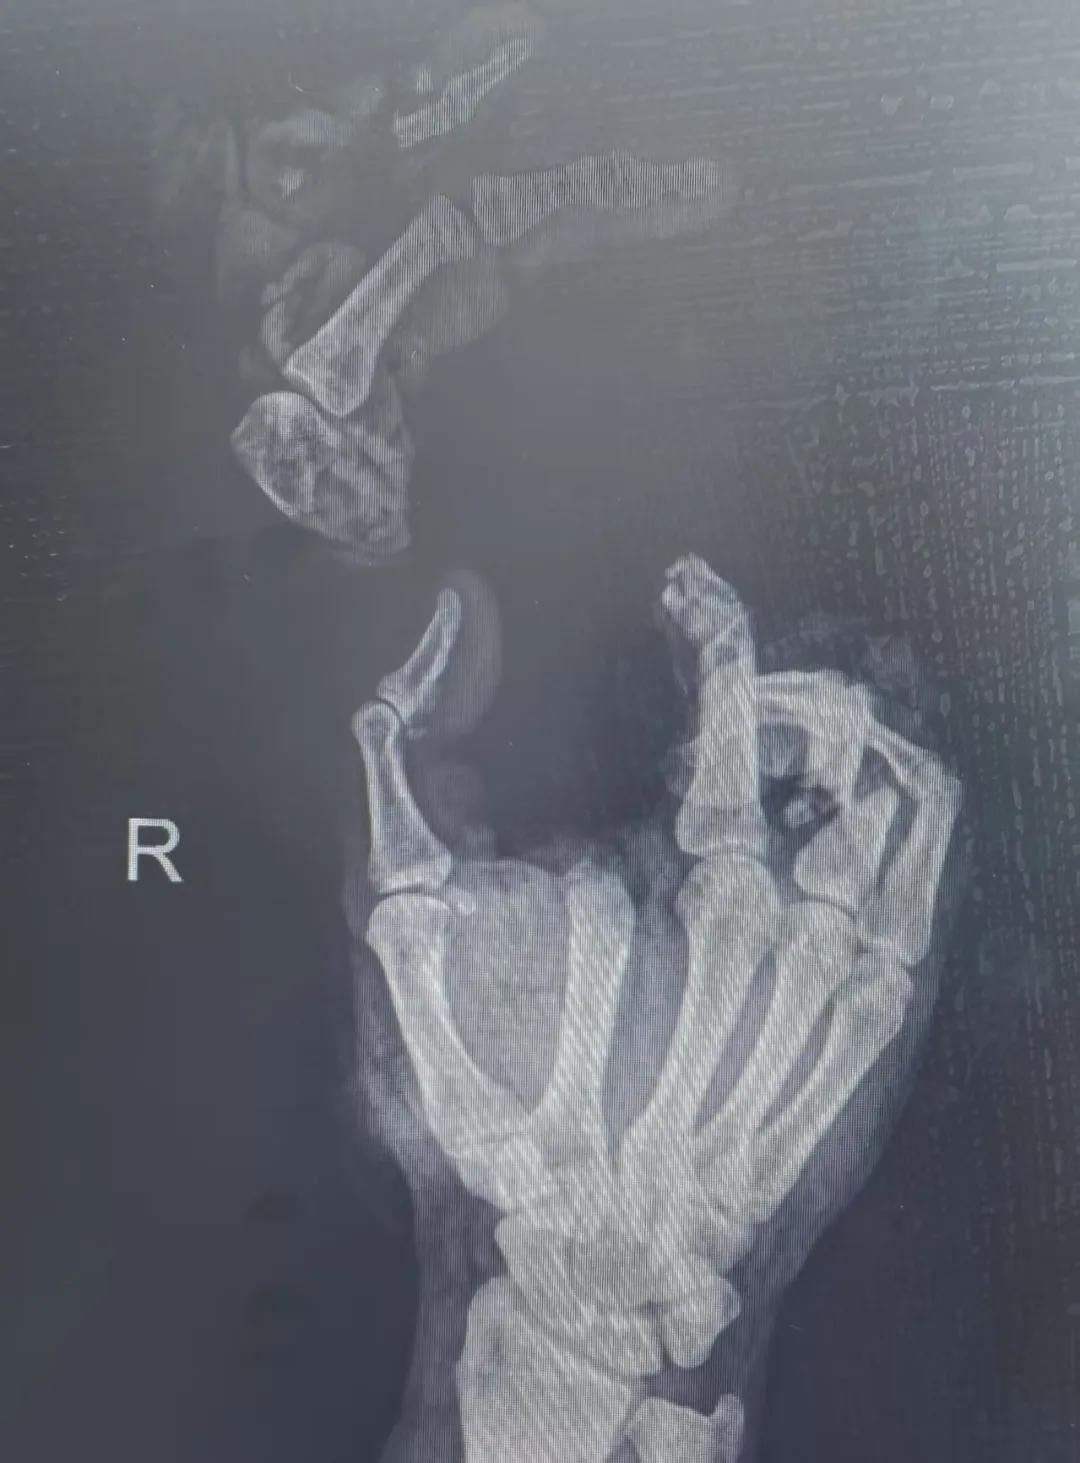

5月20日,市二院顯微外科燒傷整形科收治了3例因麥?zhǔn)毡晦r(nóng)機(jī)“咬傷”、農(nóng)具劃傷的患者。其中,56歲的劉某在收麥子時被打谷機(jī)皮帶絞傷右手,致手掌、食指、中指、環(huán)指嚴(yán)重毀損傷,骨、關(guān)節(jié)外露,因當(dāng)?shù)蒯t(yī)院無法治療,被家人緊急送往市二院顯微手足燒傷整形外科救治。“當(dāng)時整個右手血肉模糊,看上去都是爛的,我以為這個手是肯定保不住了。”患者家屬回憶當(dāng)時的場景仍然膽戰(zhàn)心驚。

患者入院后,經(jīng)X線檢查及創(chuàng)面檢查,醫(yī)生診斷為右手食指、中指及環(huán)指旋轉(zhuǎn)撕脫性離斷。接診的顯微手足燒傷整形外科醫(yī)護(hù)人員立即完善了各項術(shù)前準(zhǔn)備,并安排急診手術(shù)。因創(chuàng)面污染嚴(yán)重以及離斷肢體損傷程度較重,手術(shù)歷時近10小時。在沈衛(wèi)軍主任的帶領(lǐng)下,科室團(tuán)隊成功為其進(jìn)行了創(chuàng)面擴(kuò)創(chuàng)、斷肢再植術(shù),術(shù)后患指血運良好,在進(jìn)一步觀察治療中。